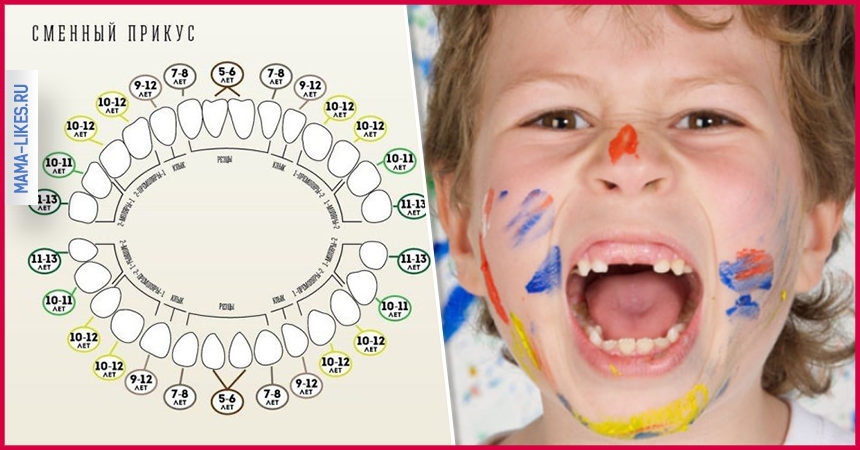

Приблизительная очередность выпадения и смены зубов:

Возраст ребенка Зубы

6 – 7 лет – Нижние, а за потом верхние центральные резцы, первые моляры

7 – 8 лет – Боковые резцы

9 – 10 лет – Первые премоляры

10 -11 лет – Прорезывание клыков, вторых премоляров

11 -13 лет – Вторые моляры

Во сколько лет выпадают молочные зубы у детей? Смена молочных на коренные начинается в среднем с 5-6 лет, но процесс, предшествующий выпадению происходит еще задолго до этого. Начиная с 4-6 лет, у ребенка рядом с молочными зубами прорезываются третьи моляры (самые дальние в зубном ряде, так называемые «шестерки»), которые являются первыми постоянными зубками.

Выпадают они в течение 5-8 лет, начиная с 5-летнего возраста и до достижения ребенком 13 лет. К 14 годам зубной ряд подростка должен состоять из всех коренных зубов.

Когда выпадают молочные зубы у детей —схема

Когда выпадают молочные зубы у детей —схема

При этом процесс, сроки и порядок выпадения будет зависеть от того, в какой последовательности и когда прорезались зубки у младенца. Чем позже появились первые зубы, тем дольше не будет происходить их смена на постоянные. Прорезываются коренные зубы симметрично с двух сторон. У девочек этот процесс начинается раньше, у мальчиков – немного позже.

В большинстве случаев зубы, находящиеся снизу, выпадают раньше, чем соответствующие им резцы, клыки или моляры, находящиеся в верхней челюсти.

Процесс смены достаточно длительный. Знание сроков помогает родителям определить причину появления болей и отека десны. Начинается этот период примерно к 6-7 годам. Продолжается смена 6-7 лет и завершается к 12 годам. Сколько именно займет период, зависит от индивидуальных особенностей ребенка и его здоровья. Примечательно, что у девочек временные зубы выпадают быстрее, чем у мальчиков.